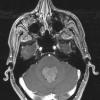

NEOPLASMS (NON-GLIAL NON-NEURONAL)

Choroid plexus papilloma (8)